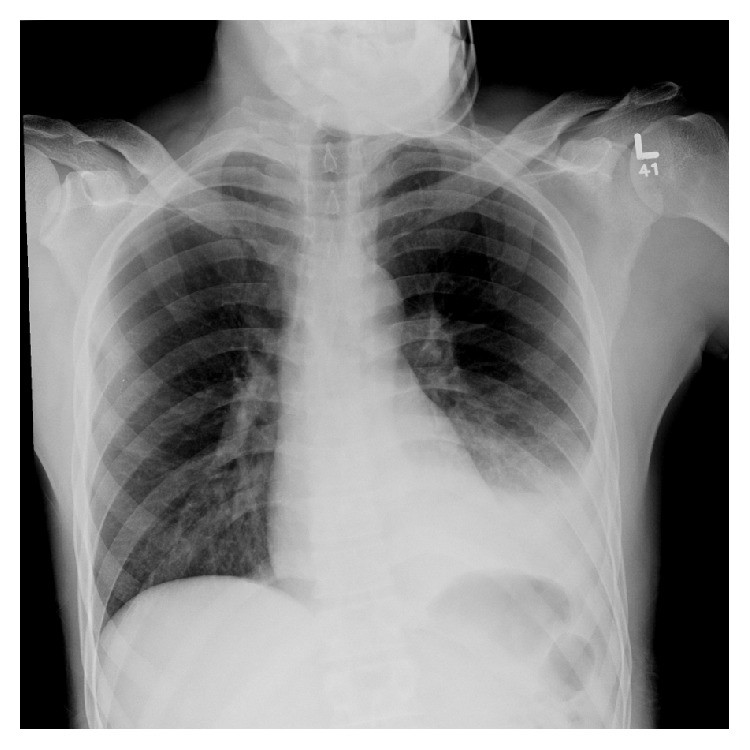

Carol O’Grady, aged 68 years, has a three-month history of increasing pain in her right shoulder, shoulder blade and upper arm. She is a keen knitter but her hand ‘isn’t working as well as it should’. Carol has been using paracetamol 1 g orally four times daily with no improvement in her symptoms. Occasionally the pain wakes her from sleep. On examination, she has generalised reduction in her shoulder’s range of motion, weakness of the grip strength in her hand and atrophy of her thenar eminence. You arrange appropriate blood tests and a chest X-ray (see image).

What is the MOST appropriate provisional diagnosis?

F. Pancoast syndrome

Correct Answer: F. Pancoast syndrome